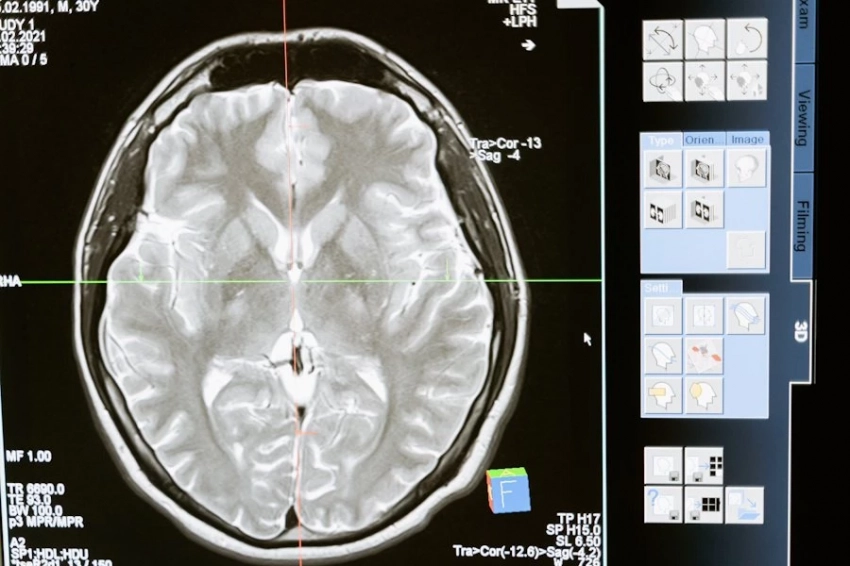

Как сообщает журнал Nature Communications, эксперты Института когнитивных и нейронаук Общества имени Макса Планка отследили связь высокого давления при оптимистическом настрое.

Специалисты изучили данные свыше 500 тысяч участников предыдущего исследования UK Biobank. Средний возраст участников — 58 лет, наблюдение длилось около девяти лет. У 135,7 тысячи пациентов на начало эксперимента уже была в наличии гипертензия.

Участники часто рассказывали, что на фоне высокого артериального давления оставались вполне бодрый и даже иногда превалировал радостный настрой. Хотя активность мозга была ниже.

Парадоксальная на первый взгляд связь. Ученые так ее объясняют. Люди могут годами жить, не зная о проблемах с давлением. Наступает привыкание, повышается порог чувствительности.

У них до начала лечения были нервные срывы на фоне усталости, депрессии как следствия повышенного давления. И лишь когда становилось совсем плохо, они обращались к врачу. Начинали лечиться, и настроение улучшалось.